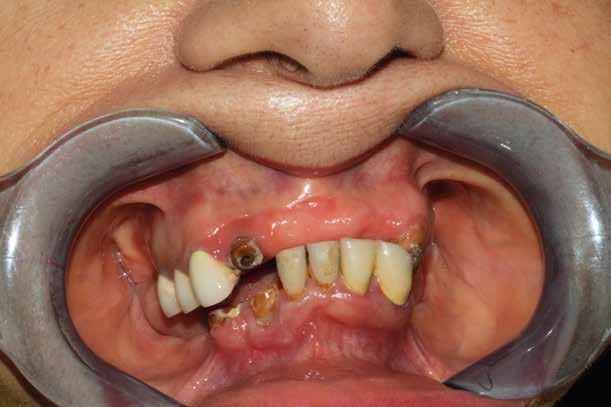

Il paziente del seguente caso, già visitato nel 2019, è poi tornato nel 2021 per una rivalutazione. Già durante la prima visita era stata rilevata una situazione di compromissione generale, sia dal punto di vista igienico, sia funzionale.

Alla visita di rivalutazione è emerso un ulteriore peggioramento della situazione, confermata anche dall’esame radiografico, con parodontopatia, sanguinamento al sondaggio, infiammazione diffusa, alitosi, difetto parodontale verticale mesiale a 2.3, residui radicolari 1.4, 1.6, 1.7, 3.6, 3.8 e carie destruenti di 1.5, 2.6, 3.5, 3.7 (con lesione endoperio) e 4.7 con estrusione e carie (Figg. 1, 2)

Il paziente, un uomo di 67 anni, ha confermato l’anamnesi precedente, ossia di essere portatore di

molteplici patologie: sindrome metabolica in discreto compenso farmacologico (riferita assunzione di metformina 500 mg, enalapril, acido acetilsalicilico, atorvastatina) e in terapia sostitutiva con levotiroxina perché operato di tiroidectomia totale per un tumore in giovane età; deambulazione autonoma con aiuto del bastone per via di un intervento al ginocchio abbastanza recente (riferito 6 mesi prima intervento di protesi totale di ginocchio).